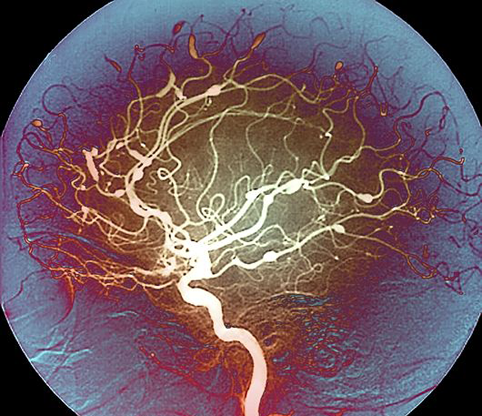

Снимки и иллюстрации микроаневризм сосудов головного мозга